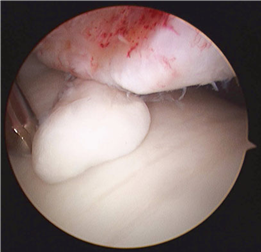

Clinical & Radiographic Imaging Archive